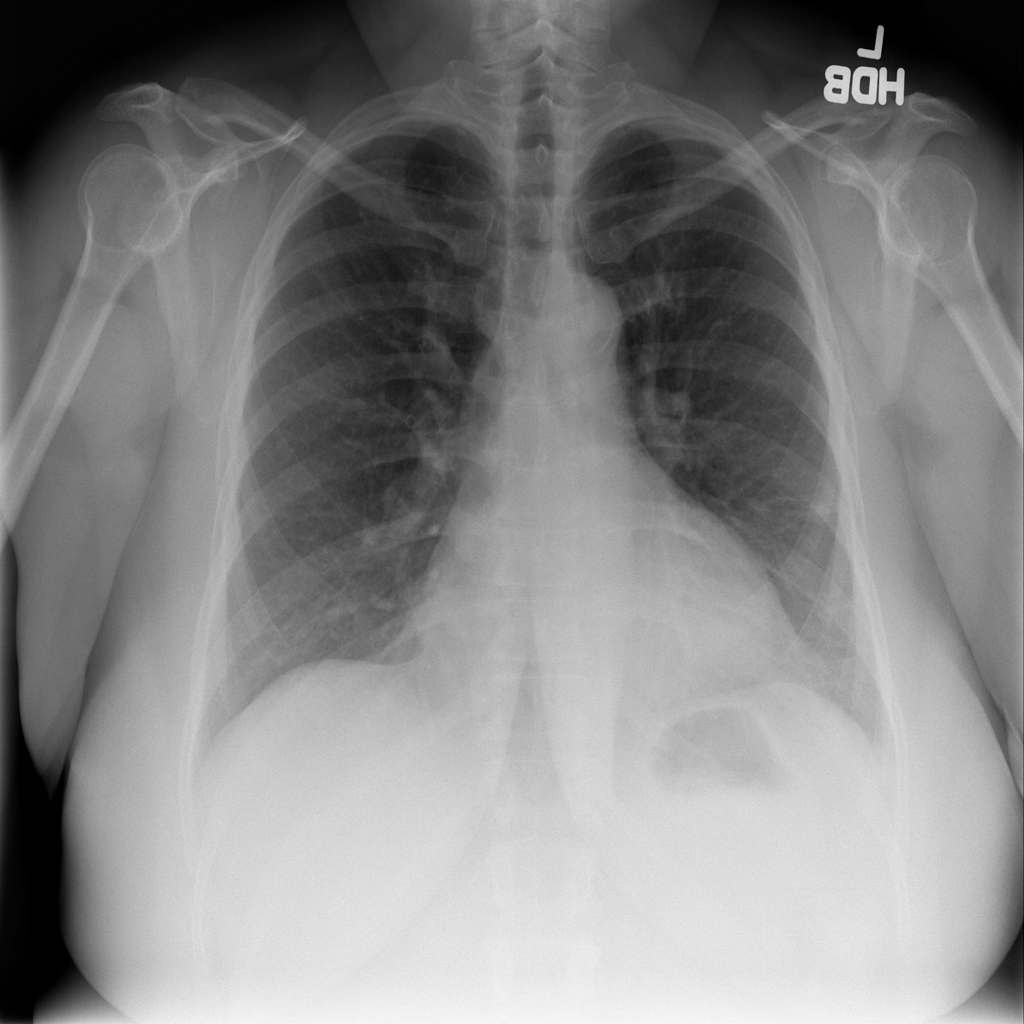

PAT-86C8 · IMG-006Atelectasis

PAT-86C8 · IMG-006

PA